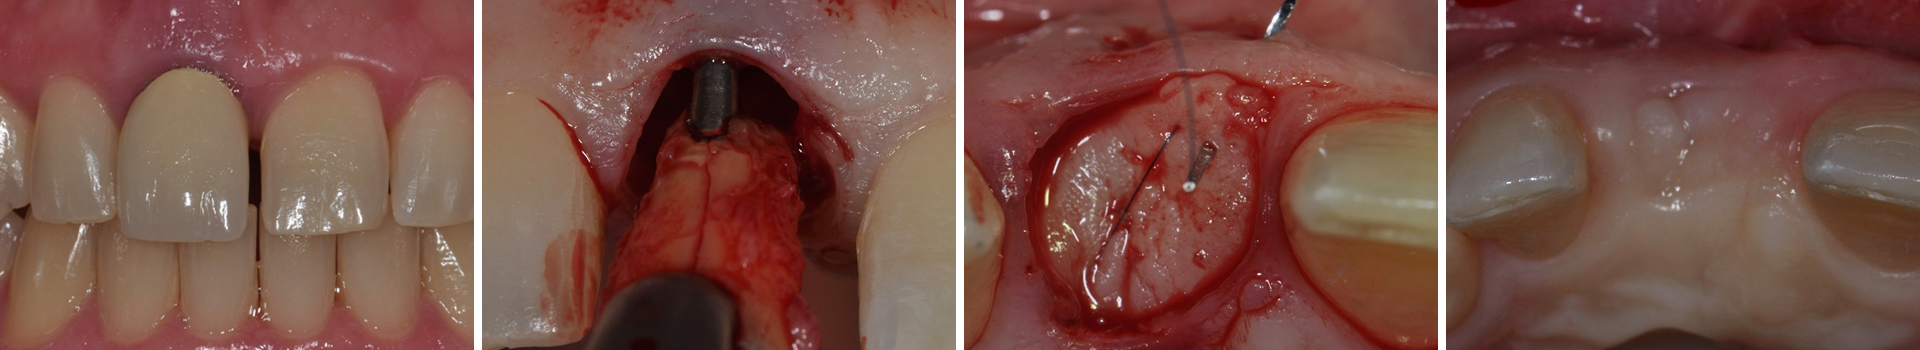

Abbildung 1

Ausgangssituation: Frontalansicht.

Abbildung 2

Der überkronte Zahn 11 ist elongiert und zeigt deutliche Entzündungszeichen mit einer vestibulären Schwellung.

Abbildung 3

Auf der Röntgenaufnahme ist eine apikale Entzündung im Sinne einer periapikalen Parodontitis zu erkennen.

Abbildung 4

Nach der Anästhesie werden die intraligamentären Fasern mit einer Mikroskalpellklinge getrennt.

Abbildung 5

Es erfolgt die vorsichtige und gewebeschonende Extraktion von Zahn 11.

Abbildung 6

Nach der Extraktion sind die Längsfraktur der Wurzel und die deutlich apikale Positionierung des Wurzelstiftes erkennbar.

Abbildung 7

Okklusale Ansicht der Extraktionsalveole. Die Entfernung des Saumepithels erfolgt mit einem grobkörnigen Diamantbohrer.

Abbildung 8

Das Saumepithel wurde entfernt und eine Blutung ausgelöst.

Abbildung 9

Das Transplantat sollte im Durchmesser etwa 1mm breiter als die Extraktionsalveole sein

Abbildung 10

Aus der Tuberregion wird nun distopalatinal des zweiten Molaren in einer Dicke von etwa 4 mm mit einer maschinellen Gewebestanze ein freies Gingivatransplantat entnommen.

Abbildung 11

Mit einem scharfen Instrument werden die Fasern durchtrennt, sodass Periost und bindegewebige Fasern am Knochen verbleiben. Dadurch wird eine Exposition des Knochens vermieden und die Heilung beschleunigt.

Abbildung 12

Abbildung 13

Um die Blutversorgung des Transplantats sicherzustellen, wird zuerst eine modifizierte Matratzennaht gelegt. Mit Hilfe von mikrochirurgischen Einzelknopfnähten wird das Transplantat anschließend mit den Alveolenrändern verbunden.

Abbildung 14

Finaler Nahtverschluss.